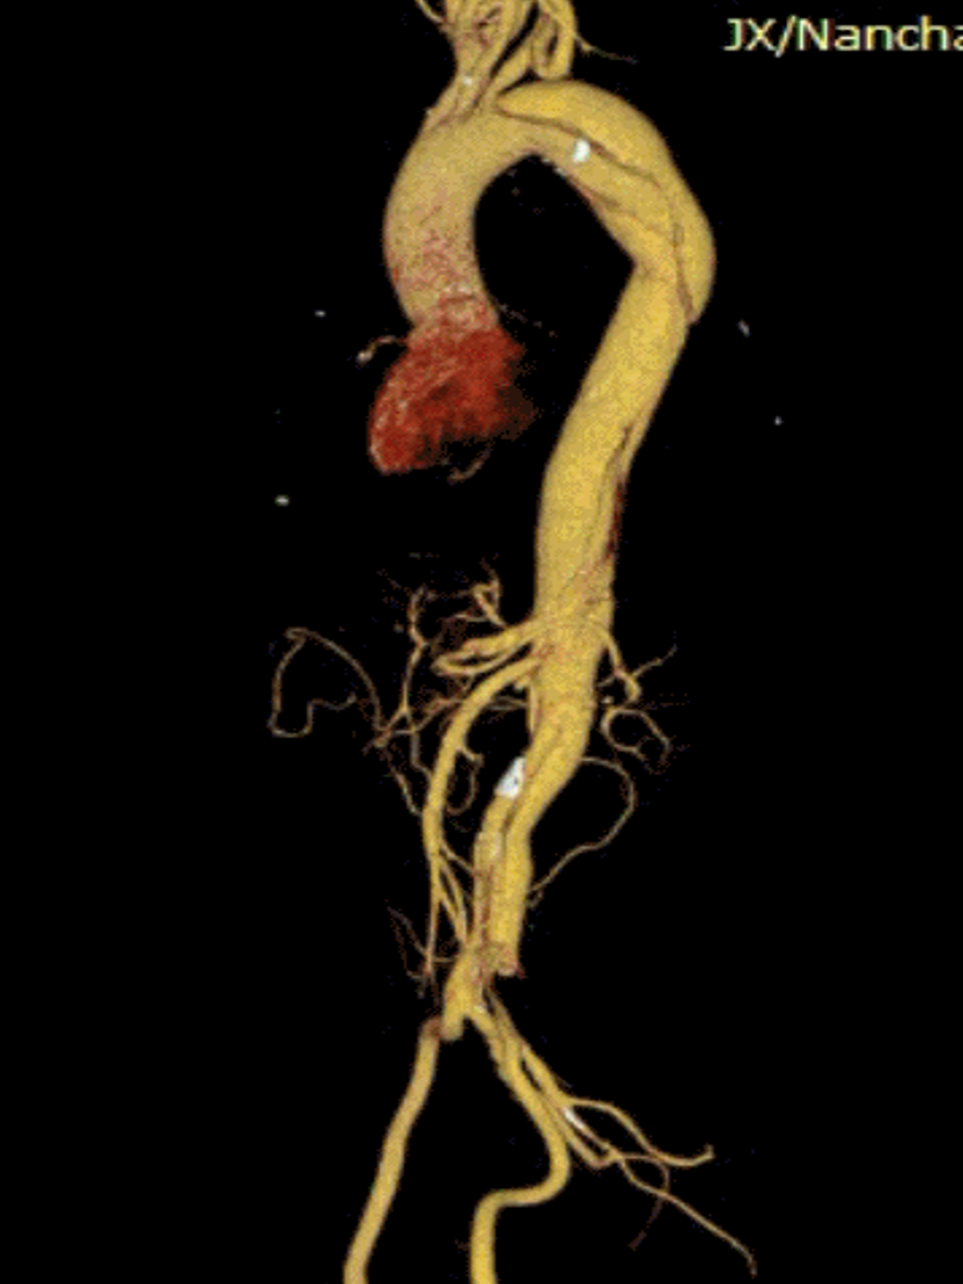

复杂病例应用:巨大弓部动脉瘤(5.5cm)且左锁骨下动脉位于瘤腔内:在预开窗基础上加做左锁骨下动脉内嵌分支,配合3D打印模型辅助和束径技术,术后随访效果理想

A型夹层合并迷走左椎动脉:针对头臂干、左颈总和左锁骨下动脉进行预开窗,对非优势且纤细的迷走左椎动脉仅作小洞处理,术中对位良好

弓部动脉瘤:Castor联合内嵌分支LSA预开窗术,目的为防内漏

避免转流的复杂病例:Castor+原位及预开窗(免转流三开窗)治疗弓部动脉瘤